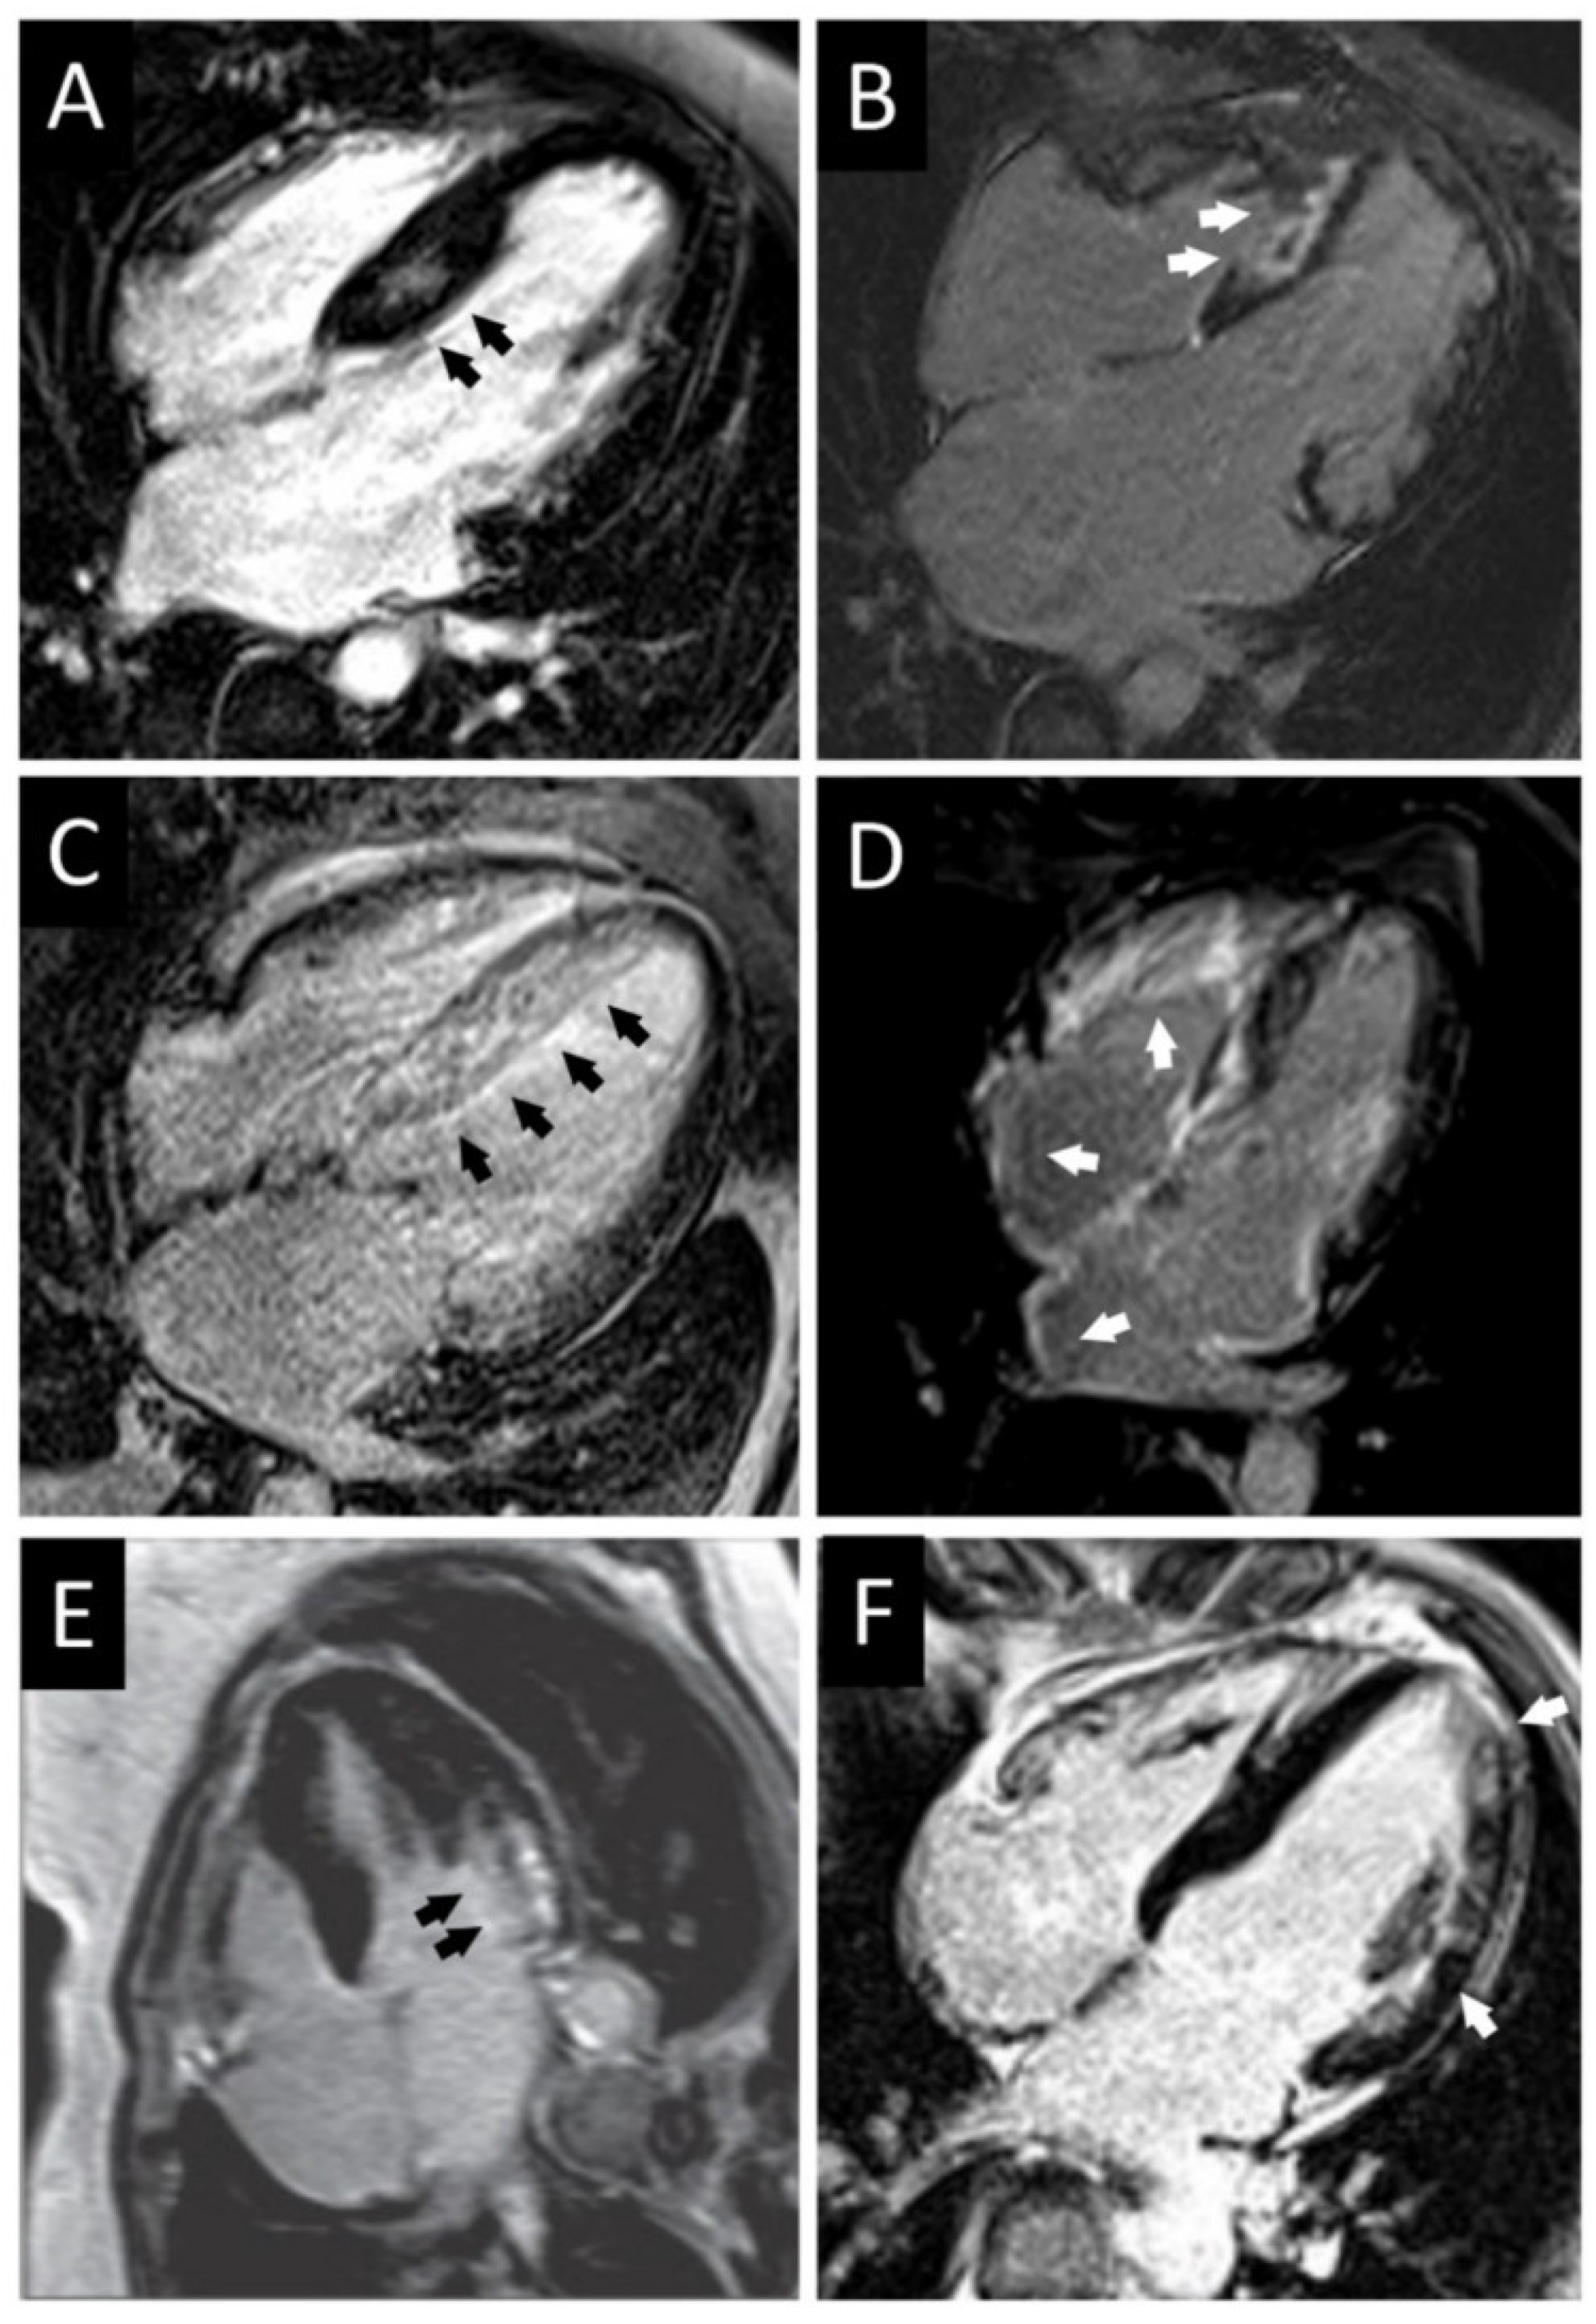

5. CMR for Risk Stratification in Adults with HCM

6. Special Considerations in Children

7. Risk Stratification in Children with HCM